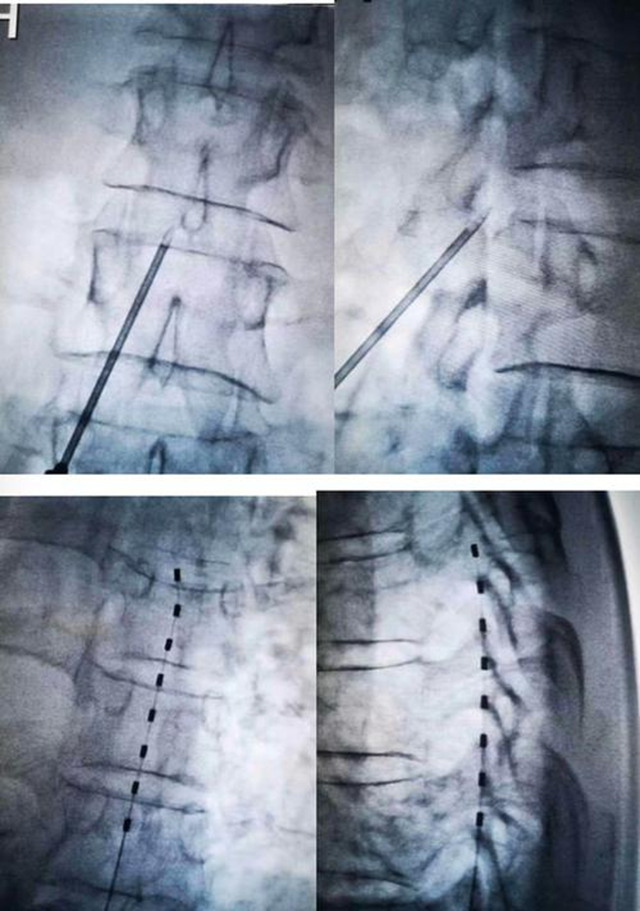

脊髓电刺激

3、脊髓电刺激术

经皮穿刺脊髓电刺激镇痛术是将电极植入脊髓硬膜外,通过电极传递电刺激,阻断疼痛信号向大脑传递,从而治疗神经病理性疼痛。该治疗通过干扰疼痛信号的传递发挥作用。